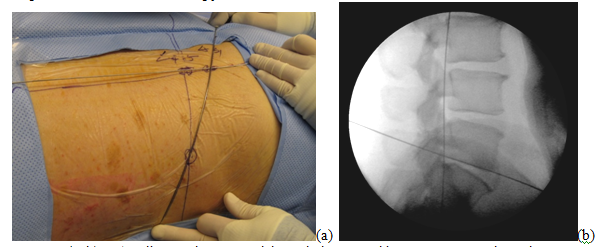

A 63-year-old patient with morbid obesity and insulin dependent diabetes mellitus suffered from spinal canal stenosis and multiple level disc protrusions at L2/3, L3/4, L4/5 and L5/S1. The largest disc was at L5/S1, > 6mm as illustrated below. His weight is 280 lbs and height 5’ 8” (Figure 4–16). The patient complained of back pain and radicular symptoms including the anterior and surface of both thighs and legs, and back of the foot with more severe pain on the right side associated with some neurogenic claudication. Previously the patient refused open surgery with fusion, because of increased risk in morbid obese and diabetic patients and requiring a multi level extensive open spinal fusion. After reviewing his MRI scans, (Figure 4) minimally invasive endoscopic microdecompression surgery was recommended to the patient as a solution for his spinal condition. He agreed to proceed with MISS surgery. It can be very time consuming to reach the foramen in obese patients since the fat distribution gives a false orientation of the actual location of the spine in relation to the skin surface. By using the GPS system to triangulate the 3D orientation of the foramen under fluoroscopy, the height, width and depth of the soft tissue in relation to the foramen was determined the microdecompression was successfully performed. Bilateral L2-L5 endoscopic microdecompressive discectomy (Figure 5–16) was performed in the lateral decubitus position on two sittings of less than 1 hour for each side to avoid a prolonged single procedure. The patient reported marked relief of his back symptoms and lower limb numbness on the next post operative day with a better range of motion and ambulation.

Figure 7 (a, b) L5/S1 disc can be accessed through the same skin puncture entry through a steeper angle, on patient and under fluoroscopy.

Note: L4/5 disc portal of entry point can be used to access both L4/5 and L5/S1 discs by applying different angles to the trajectory of the stylette, perpendicular (for L4/5 disc) vs. steeper angle (for L5/S1 disc).